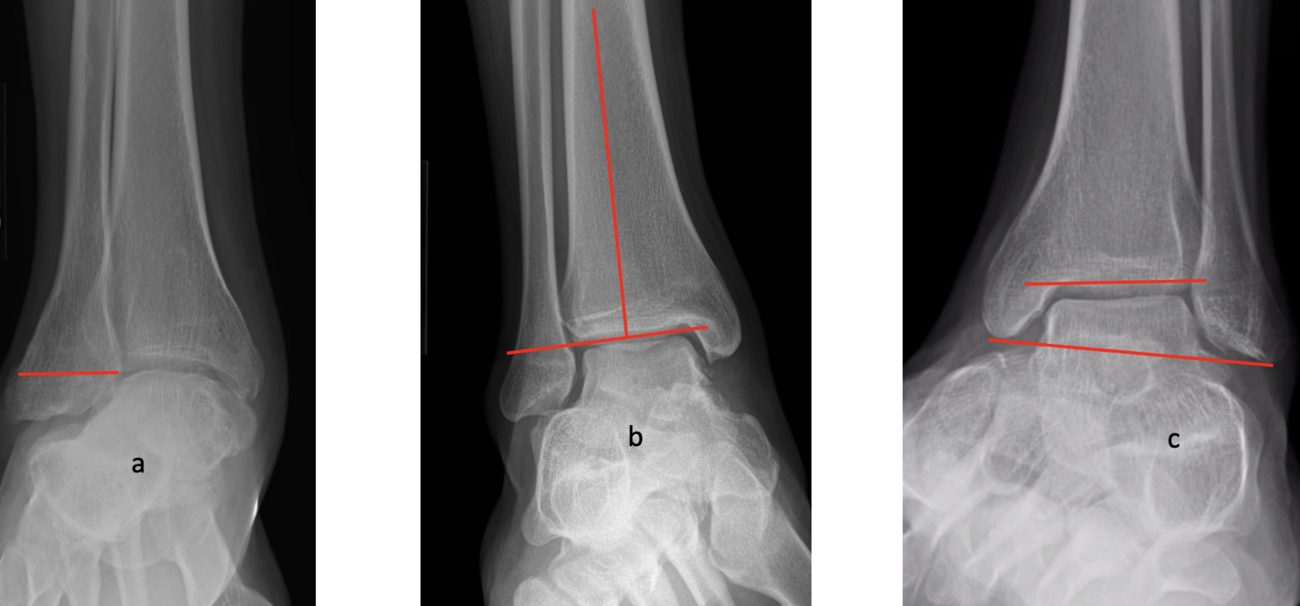

One of the most disturbing complications with any casting is the development of flat top talus. Overly aggressive attempts to dorsiflex the ankle often lead to met primus elevatus, but the flat top talus ruins the ankle joint during development. When I work with residents and students, I always stress the importance of avoiding dorsiflexion completely during the casting phase simply because I do not want to create a deformation of the talus. I reserve all of my sagittal plane correction for the Achilles lengthening and posterior capsule release. Unfortunately, I see more and more cases of flat top talus as a result of the Ponseti method. Khan and colleagues in 2021 reported a significant increase in their study and review of the literature, blaming it solely on overly aggressive casting and manipulation.16

So, to summarize, true congenital clubfeet have abnormal talar bodies, which lead to abnormal ankle and subtalar joints with short Achilles and tight posterior tibial tendons. Regardless of treatment, there is nothing anyone can do to make the talus a normal bone. Many of these cases can and will develop additional deformities. Only the Cincinnati release can address every issue associated with the deformity, but it is NOT a cure. The Ponseti procedure is a total compromise, also NOT a cure. The sooner everyone treats the Ponseti as a compromise, I believe we will be far happier with the outcomes. I remember discussing this with others treating pediatric orthopedic issues during the rise of the Ponseti in the early 2000s. We all agreed, undercorrecting the deformity will lead to more surgeries and residual deformities. Until we all face the reality that clubfeet are a genetic deformity and not just a positional deformity, we will never make them perfect. Thus, athletes and the military will put any and all clubfeet patients to the test. There is no doubt that exceptions exist, but in time, at least based on our limited review of over 1000 clubfeet and 250 cases we saw in the military, no one is immune to complications, arthritis, and ultimately disability.

Here is a typical case presentation. A 21-year-old Marine at Ft. Leonard Wood for training underwent a Cincinnati release at one year old and had stellar follow-up. Her surgeon even wrote her medical waiver for entrance into the Marines. She ran track in high school. She finished boot camp and completed all of her Marine training, but now has chronic pain. She no longer can run. She hasn’t passed her physical training in over a year. She developed talonavicular DJD. By all accounts, her overall clubfoot should be rated an A+; no residual deformity, normal talocalcaneal angles on AP and lateral views, no equinus, no residual varus, only slight met primus elevatus, but no signs of a flattop talus. Clinically, she lacks subtalar range of motion, which I commonly find post-clubfoot release of any kind. So many in the military do very well for a while, but the demands of the military eventually catch up to them. We all root for clubfeet to make it, but the odds are stacked against them.